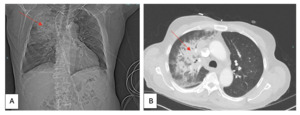

On arrival, he presented with a blood pressure of 127/55, a respiratory rate of 20 breaths/min, and an oxygen saturation of 89% on a high-flow nasal cannula. The patient was not in acute distress and auscultation of the lungs was unremarkable. Laboratory test results revealed a leukocyte count of 14.5 x 109 cells/L (reference, 4.0-10.7 x 109 cells/L) with neutrophilic predominance, hemoglobin of 8.7 g/dL (reference, 13.3-17.5 g/dL), procalcitonin of 3.88 ng/mL (reference, <=0.10 ng/mL) and creatinine of 1.95 mg/dL (reference, 0.71-1.16 mg/dL). Urinalysis was positive for 2+ protein and 3+ blood. Additionally, an acid-fast bacillus (AFB) test was obtained. Chest radiography (CXR) showed airspace and interstitial opacification of the right upper lobe with trace left pleural effusion with considerable worsening in the degree of right upper lobe consolidation with newly found infiltrate in the medial aspect of the right lower lung zone and left lung base in a subsequent CXR a day later (Figure 1). Computed tomography angiography of the chest also confirmed dense consolidations in the right upper lobe with scattered ground-glass opacities, concerning for multifocal pneumonia (Figure 2).

_initial_chest_radiograph_showing_interstitial_opacification_(arrow)_of_the_right_upper.png)